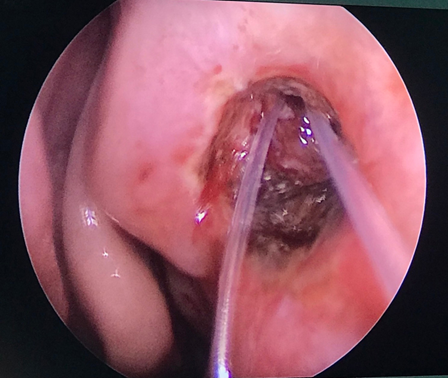

Vừa qua khoa Mắt - Bệnh viện Đa khoa tỉnh vừa tiếp nhận vầ điều trị Bệnh nhân nữ 49 tuổi vào viện vì xuất hiện khối sưng nề góc trong mắt trái kết hợp chảy mủ và chảy nước mắt nhiều. Tại đây bệnh nhân được xác định chẩn đoán Mắt trái: Viêm mủ túi lệ/ Tắc lệ đạo, bệnh nhân đã được điều trị nội khoa tích cực, triệu chứng lâm sàng giảm dần. Khoa Mắt và khoa Tai mũi họng đã kết hợp phẫu thuật cho bệnh nhân bằng phương pháp Nối thông túi lệ mũi bằng nội soi. Phẫu thuật này đã tạo đường thông trực tiếp từ túi lệ sang khoang mũi nhằm dẫn nước mắt từ mắt sang mũi. Sau phẫu thuật 2 ngày, các triệu chứng lâm sàng của bệnh nhân thuyên giảm và được ra viện sớm.

Hình 2. Mở lổ thông từ túi lệ-khoang mũi